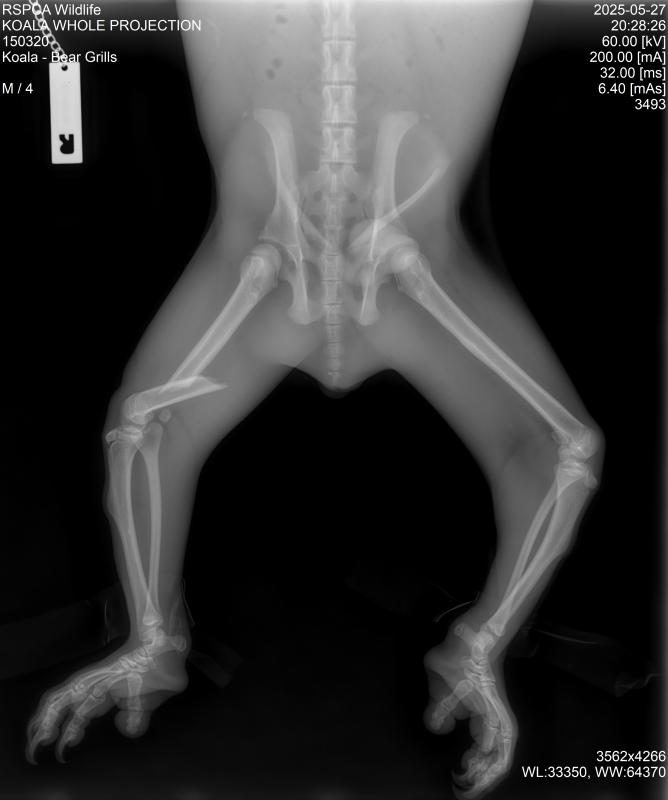

“I’m pleased to report that Bear Grills is healthy and recovering well after undergoing surgery for a fractured thigh,” Ms Colbran said.